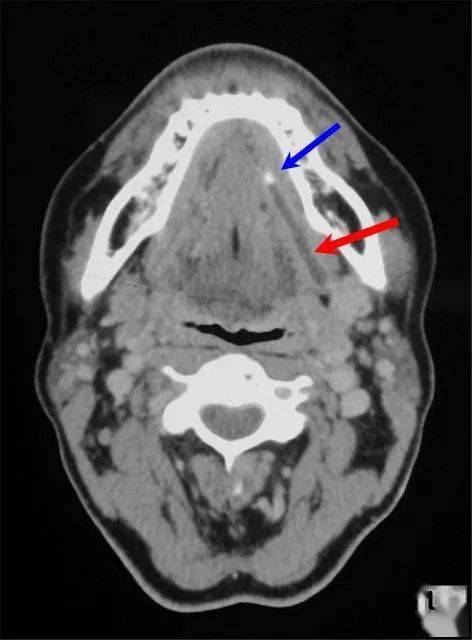

涎石症影像学诊断